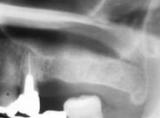

| サイナスリフトとはインプラントをするために、上の奥歯の骨が無い時に行う再生療法です。(POIワイドタイプインプラント使用) | ![]() |

【術前】 |

【術後】 |